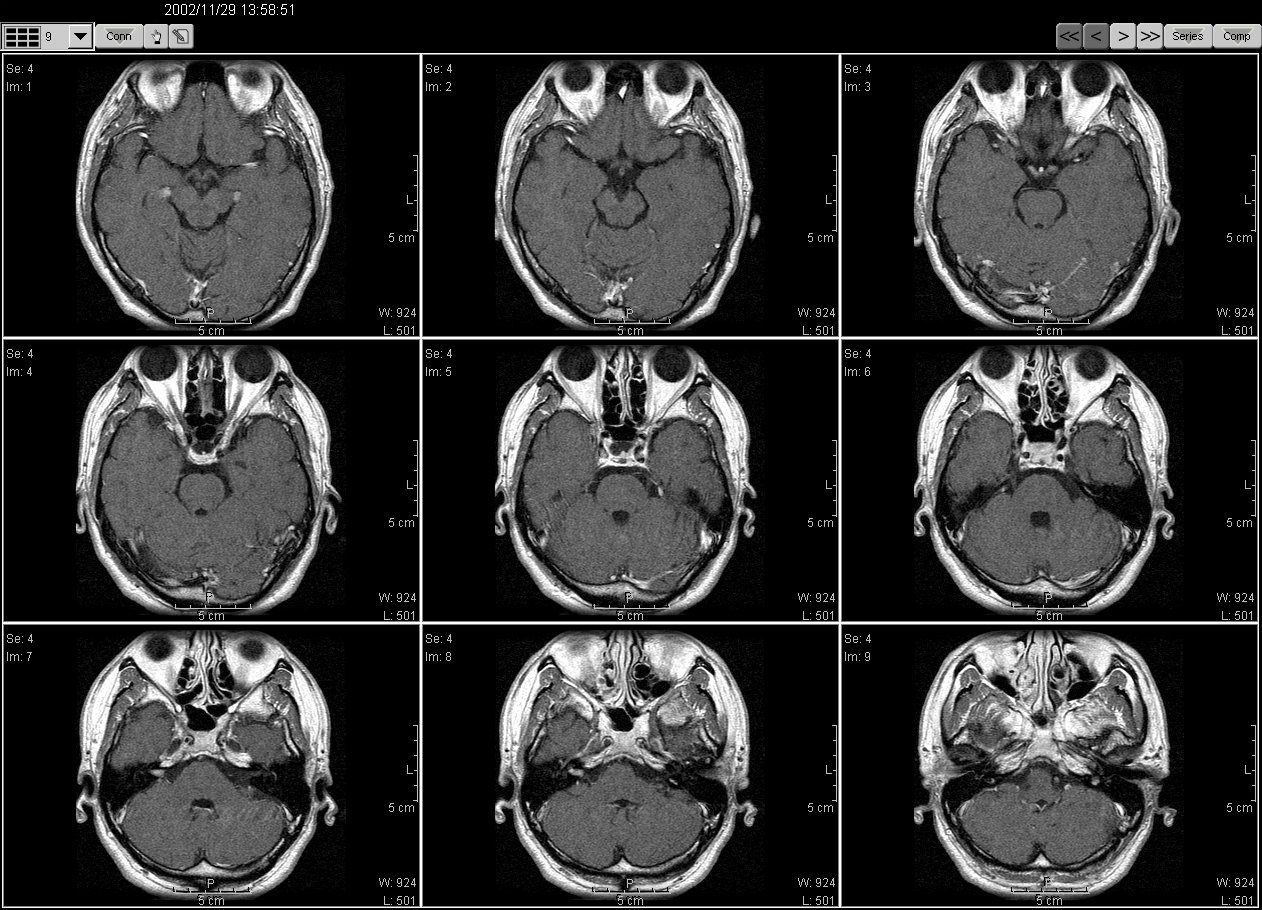

2002_11_11MRI01

2002_11_11MRI02